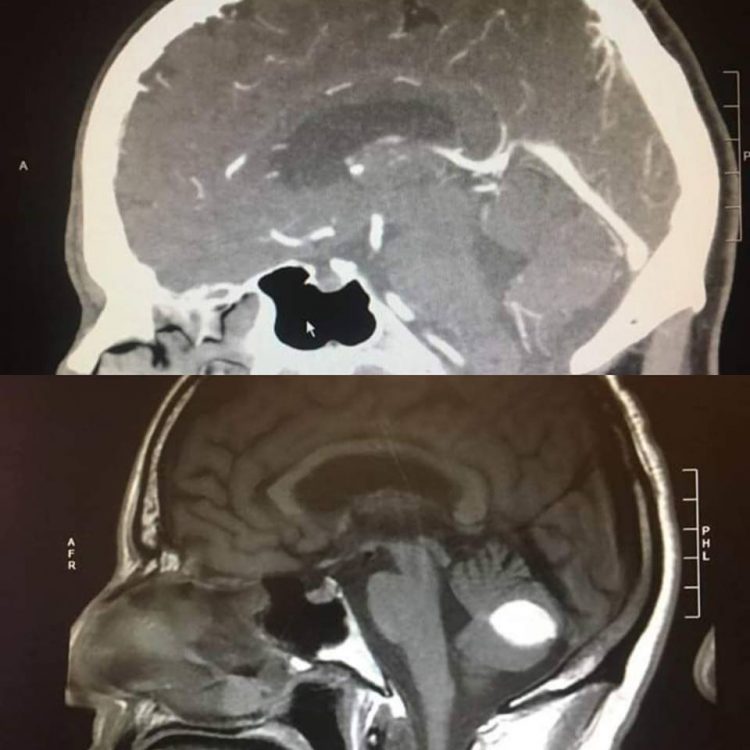

A California man’s unexpected recovery has left doctor’s baffled. A day before his scheduled surgery to have a presumed brain tumor removed, a final head CT exam showed that the mass in his brain had miraculously disappeared.

Paul Wood, a resident of Lodi, in California, started complaining of excruciating headaches and dizziness several months ago, and received several serious diagnoses from doctors. A neurosurgeon at UC San Francisco told him that he had a brain bleeding, while a radiologist told him that his CAT scans showed a brain tumor. Both required risky brain surgery, but a day before the scheduled intervention to have the suspected tumor removed, a fresh CT scan revealed no sign of anything unusual in his brain. Doctors couldn’t, and still cannot explain what happened, but Wood is convinced that it’s nothing short of a miracle from God.

Doctors can’t really dispute Wood’s theory, as they cannot logically explain what happened to the clear white spot visible on his initial brain scans. They have reportedly asked Paul to take part in further research so that they can learn more about what happened.